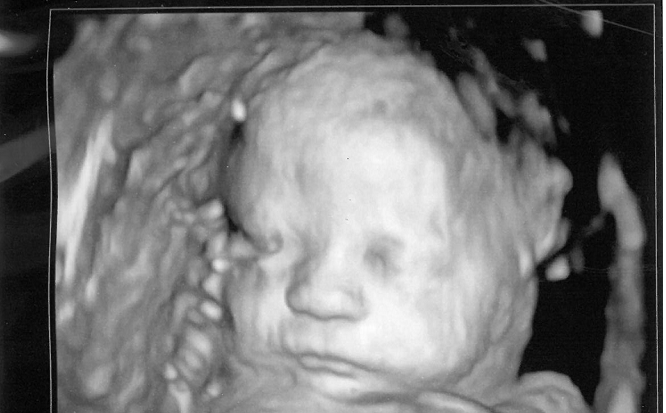

Crystal Holcombe and her unborn baby were shot and killed, along with 24 others Nov. 5 at the First Baptist Church of Sutherland Springs, according to the Religion News Service.

Texas recognized Holcombe’s unborn child, who was nearly full term, as one of the victims because of its 2003 Unborn Victims of Violence Act, the report states. The state law extends the protections of the entire criminal code to “an unborn child at every stage of gestation from fertilization until birth.”